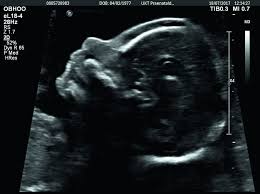

An ultrasound can detect fluid at the back of a fetuss neck which sometimes indicates Down syndrome. During the first trimester this combined method results in more effective or comparable detection rates than methods used during the second trimester.

An ultrasound can detect fluid at the back of a fetuss neck which sometimes indicates Down syndrome. Ultrasound alone cannot diagnose Downs Syndrome however there are features which can be soft markers suggestive of Downs Syndrome. During the first trimester this combined method results in more effective or comparable detection rates than methods used during the second trimester. Ultrasound can detect fluid at the back of a fetus neck which can be an indicator of down syndrome. By itself the test does not tell. October 15 2018 Shane Dale According to the National Down Syndrome Society NDSS during the normal fertilization of a womans egg by a mans sperm the resulting nucleus of each cell in a fetus contains 23 pairs of chromosomes half of which are inherited from each parent. Can Prenatal Ultrasounds Accurately Detect Down Syndrome. Down Syndrome can include. This is because certain minute birth defects cannot be picked up by an ultrasound.

Certain findings sometimes called soft markers on ultrasound may make your doctor more suspicious that your baby may have Down syndrome. An ultrasound can detect fluid at the back of a fetuss neck which sometimes indicates Down syndrome. Yet major congenital deformities are detected during fetal life. This is an effective method in the early detection of health disorders. This is because certain minute birth defects cannot be picked up by an ultrasound. Mothers should not be encouraged to have an ultrasound called a. An ultrasound can detect fluid at the back of a fetuss neck which sometimes indicates Down syndrome.